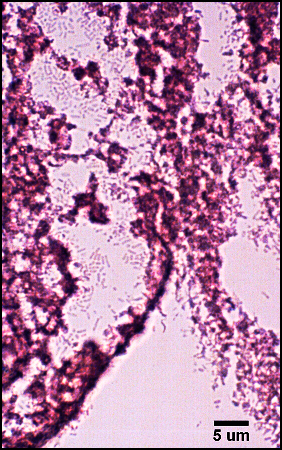

The predominant type of biofilm bacteria observed using light microscopy were Gram positive cocci (Figure 7-4). These results were in agreement with culture data which showed a predominance of Staphylococcus and Enterococcus from these patients. SEM examination of the samples confirmed the predominance of coccoid cells, which often appeared to be coated with EPS (Figure 7-5). Similar coatings were observed in pure culture biofilms of Staphylococcus aureus grown using the colony biofilm model (Figure 7-6).

Biofilms composed of Gram-negative rods (Figure 7-7) and mixed-species biofilms (Figure 7-8) were also observed. These results were confirmed by results of culture and molecular analysis, discussed below, indicating that wound biofilms are indeed polymicrobial.